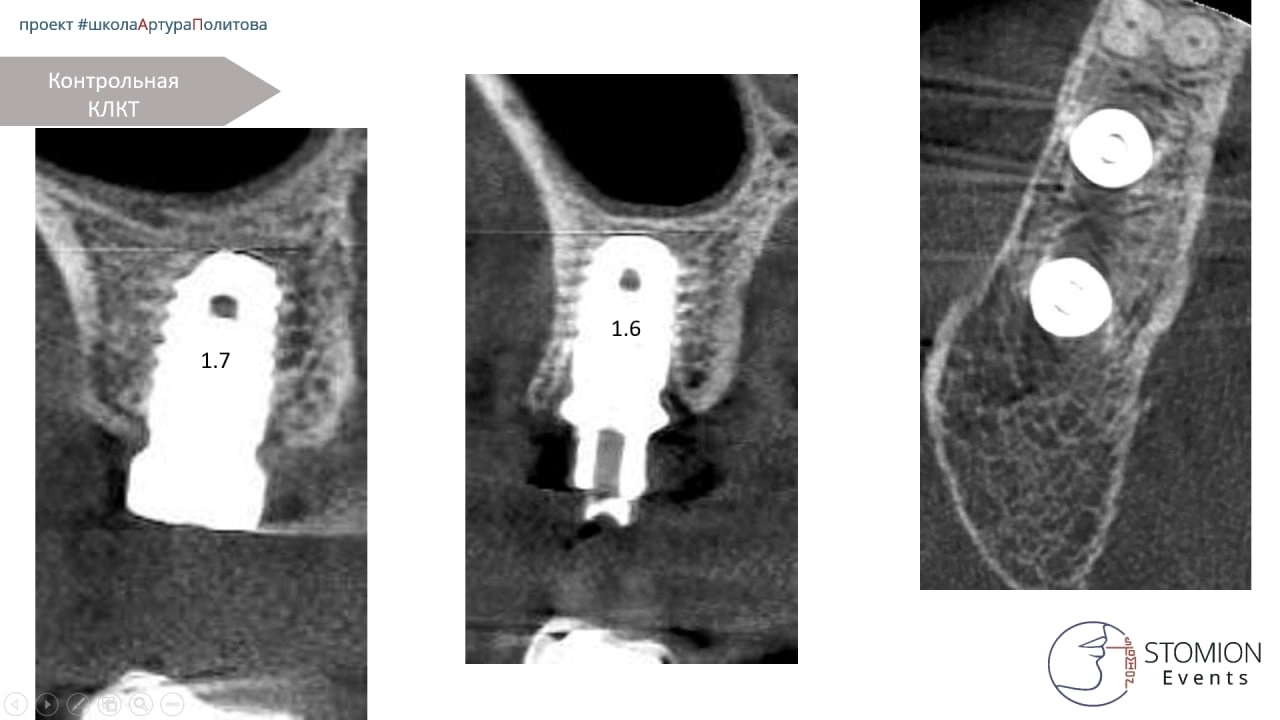

— Через 3 месяца проведена имплантация в области 1.6 и 1.7.

— Установлена временная конструкция с уровня мультиюнита.

Однако через 3 месяца выявлено отсутствие остеоинтеграции имплантата в позиции 1.7. Проведено удаление и повторная установка по тому же шаблону.

Результаты

— Через 3 месяца отмечена стабильная интеграция имплантатов в обеих позициях. Изготовлена постоянная ортопедическая конструкция.